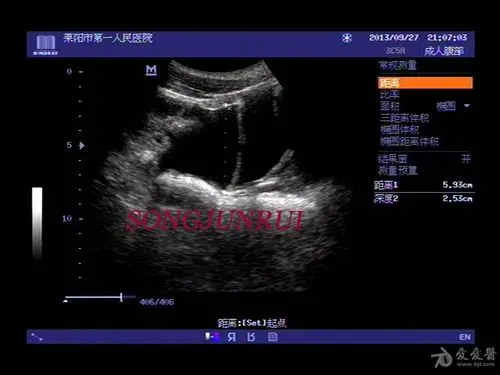

【超声】肝破裂超声,请战友欣赏

超声入门贴157肝破裂